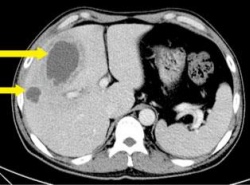

"°£¿¡ °í¸§Â÷´Â '°£³ó¾ç' Áõ°¡¼¼¡¦´ç´¢¡¤°í·ÉÀÌ ¿äÀÎ"

"°£¿¡ °í¸§Â÷´Â '°£³ó¾ç' Áõ°¡¼¼¡¦´ç´¢¡¤°í·ÉÀÌ ¿äÀÎ" °µ¿°æÈñ´ëº´¿ø ºÐ¼®°á°ú, ¿¹¹æ¹ý ¾ø¾î Á¶±â¹ß°ßÀÌ ÃÖ¼± (¼¿ï=¿¬ÇÕ´º½º) ±è±æ¿ø ±âÀÚ = ´ç´¢º´ ¹× °í·ÉÀα¸ Áõ°¡¿Í °ü·Ã¼ºÀÌ Å« 'È³ó¼º °£³ó¾ç' ȯÀÚ°¡...